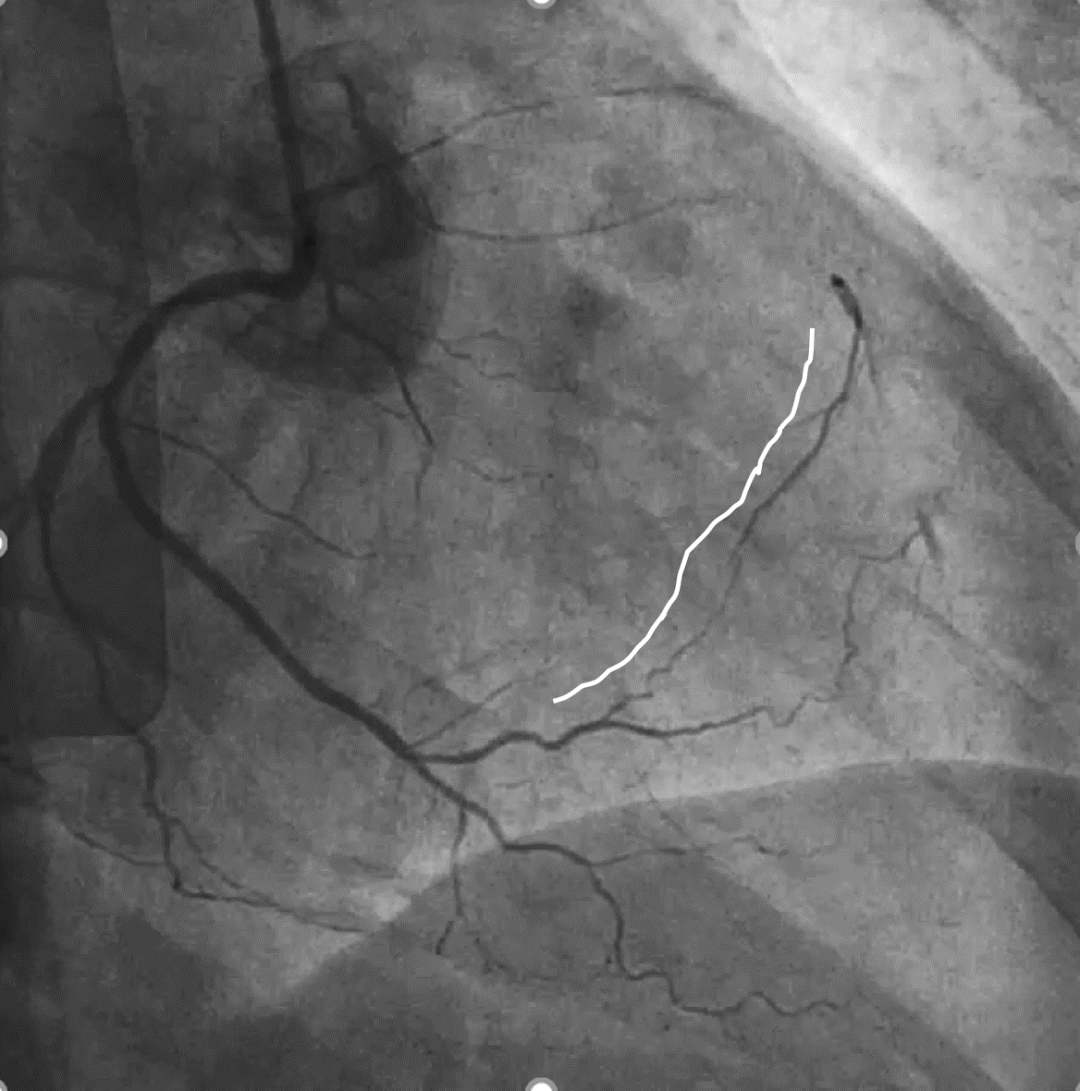

手术影像

左冠优势,LM、LCX未见狭窄,TIMI3级;LAD近段CTO,TIMI0级

RCA细小,近中段狭窄40%-50%,TIMI3级;远端可见LAD侧枝血流

策略讨论:近端纤维帽不清晰,LAD中段显影可见,闭塞段长度>20mm。间隔支逆供条件尚可。CTA提示LAD多发钙化。尝试正向开通,优选亲水性滑导丝,若失败,及时调整逆向策略。

LAD、LCX双支 CTO ,LAD 近端50%狭窄

RCA粗大,支架代偿良好。远端60%狭窄,PDA开口80%狭窄

策略讨论:双支CTO,闭塞段残端清晰,钙化,右冠造影可见PLV/PDA侧供LCA。由于有前降支PCI失败史,该次已经做好充分准备,大概率需要逆向PCI。